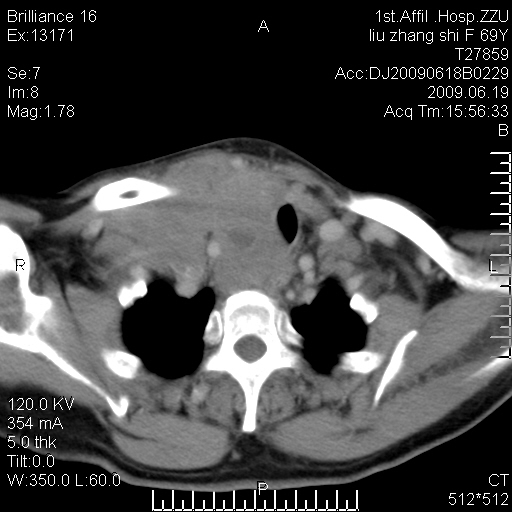

标题: CT26782:女,69岁,颈部占位,3天后公布病理结果。

【病理证实系列】女,69岁,颈部占位,有病理结果,3天后公布。(由于病例时间较久,临床资料不全,请网友见谅)本系列将有几百种常见、少见及罕见病例,均经病理证实。病例资料来自郑州大学第一附属医院。与网友共享,本人有空就发。

甲状腺癌并颈部淋巴结转移。感谢楼主的良苦用心,谢谢。

甲状腺癌并颈部淋巴结转移。

需与鼻咽癌鉴别!

支持甲状腺癌广泛侵及周围结构并颈部淋巴结转移。

鉴别:淋巴瘤、恶性神经源性病变、恶性纤维组织细胞瘤。

病理结果:颈部非霍奇金淋巴瘤。

右侧甲状腺确实有问题